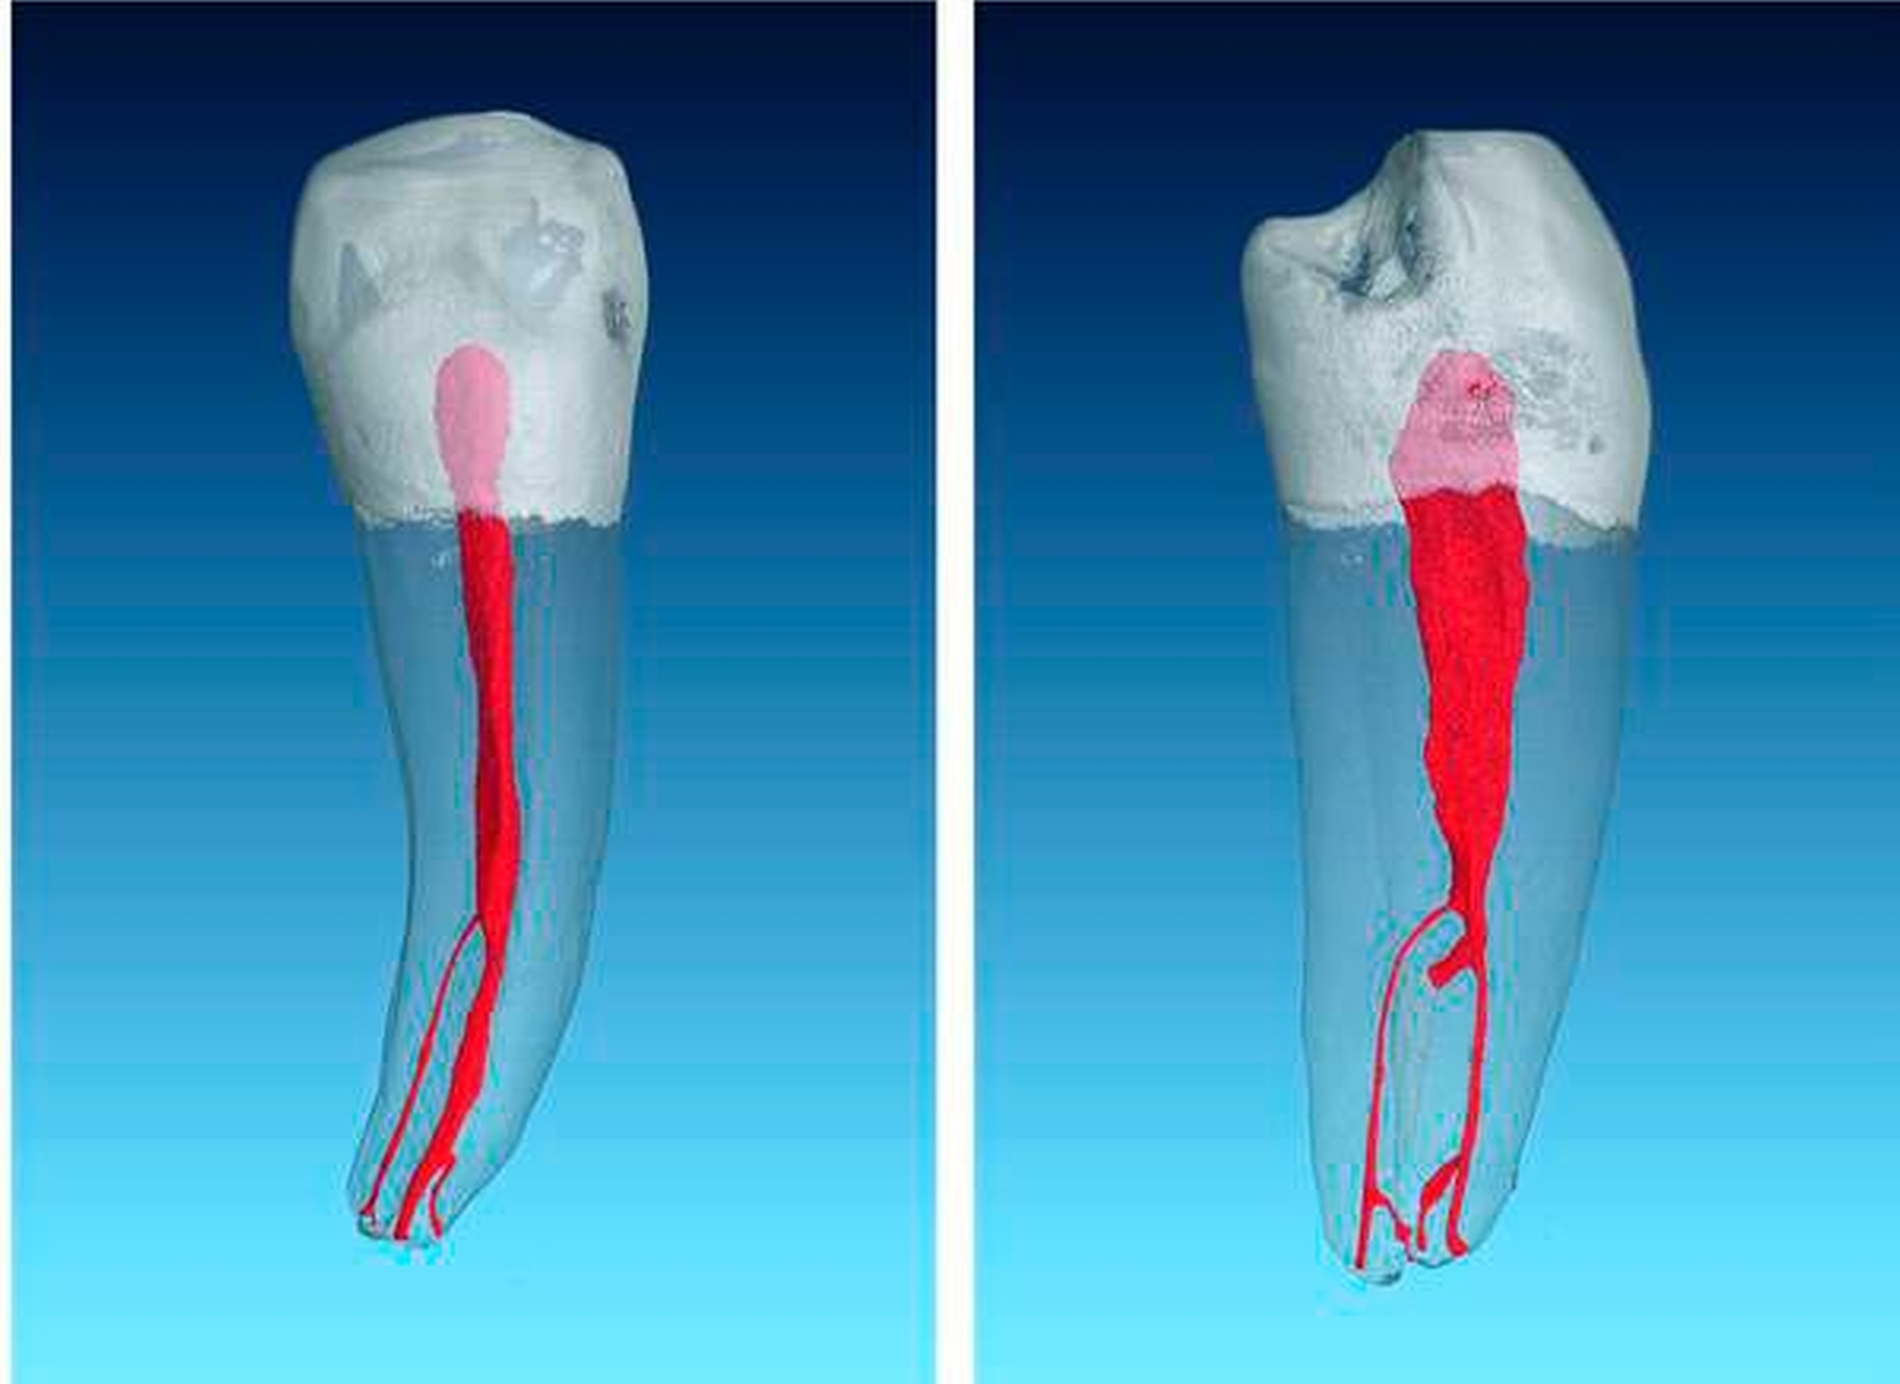

In einer Übersichtsarbeit, die acht Studien über die Anatomie von ersten Unterkiefer-Prämolaren zusammenfasst, ergab sich eine Prävalenz von mehr als einem Kanal in 24,2 Prozent aller Fälle [Cleghorn et al., 2007a]. Dabei überwiegen die zweikanaligen Prämolaren, die Prävalenz von drei Kanälen liegt bei unter 1 Prozent [Bürklein et al., 2017] (Abbildungen 4 und 5). Bei den zweikanaligen Zähnen zeigt sich üblicherweise ein weitlumiger Kanal von koronal nach apikal, von dem im mittleren oder im apikalen Drittel ein kleinerer lingualer Anteil abzweigt. Dieses Phänomen kann sehr ausgeprägt sein und macht die Behandlung extrem schwer (Abbildung 6).

Auch das Vorliegen anderer Wurzelkanalkonfigurationen, wie ein C-förmiges Kanalsystem, wird in der Literatur als nicht selten beschrieben. So zeigten Baisden et al. [Baisden et al., 1992] in einer Studie an 106 unteren ersten Prämolaren, dass in 14 Prozent der Fälle ein C-förmiges Kanalsystem gefunden wurde (Abbildung 7).

Die ersten unteren Prämolaren weisen in etwa 25, die zweiten unteren Prämolaren in etwa 10 Prozent der Fälle ein zusätzliches linguales Kanalsystem auf. Der Abzweig vom bukkalen Hauptkanal vollzieht sich meistens erst im mittleren oder im apikalen Wurzeldrittel und ist sehr schwer zu diagnostizieren und zu behandeln. Liegt eine solche Kanalkonfiguration vor, ist der Einsatz eines Dentalmikroskops für die Erschließung und die Bearbeitung lingualer Kanalanteile unumgänglich.